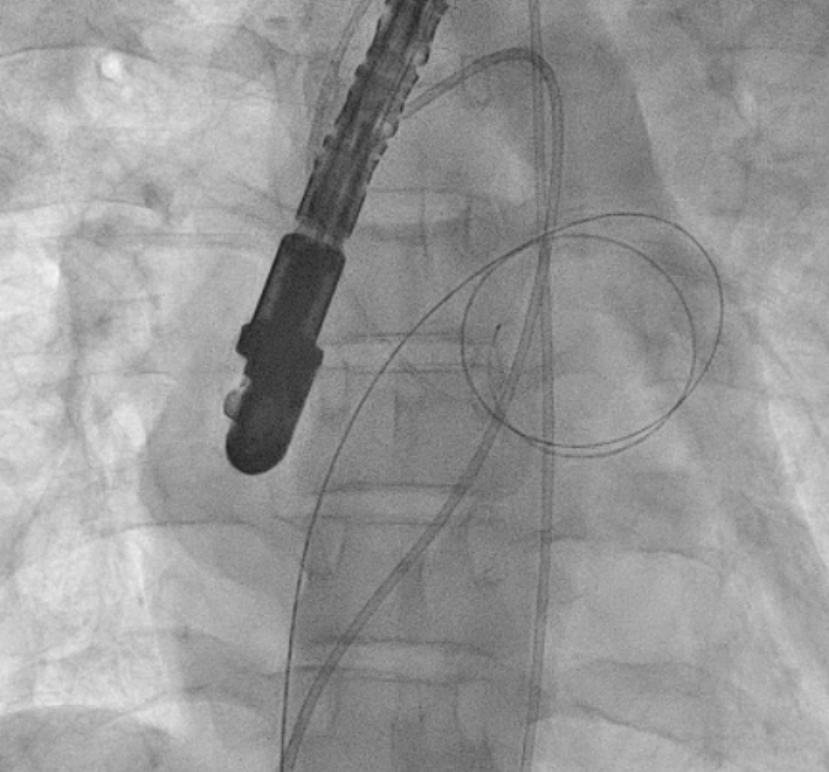

Given prohibitive surgical risk, high-risk BMV was attempted. Bilateral carotid angiography was performed and SpiderFx embolic protection devices (Medtronic, USA) deployed. Under TEE guidance, transseptal puncture was done, and an Inoue balloon (Toray, Japan) was advanced across the mitral valve. Sequential dilatations reduced the mean gradient with no embolic debris in filters. The patient improved hemodynamically and was discharged in stable condition.

The patient was deemed prohibitive risk for surgical mitral valve replacement with clot extraction, so a high-risk percutaneous approach was planned. Bilateral carotid angiography was performed, and 5 mm SpiderFx embolic protection devices (Medtronic, Minneapolis, MN, USA) were deployed to minimize embolic risk. Transseptal puncture was guided by transesophageal echocardiography because of a thin interatrial septum. An Inoue balloon catheter (Toray, Tokyo, Japan) was advanced across the mitral valve, and sequential graded dilatations were performed under fluoroscopy. Mean transmitral gradient fell markedly, with corresponding fall in pulmonary artery pressure. The embolic filters were retrieved without visible debris. The procedure was uneventful, with no neurological events. The patient was extubated on table, remained hemodynamically stable, and reported significant symptomatic improvement. She was discharged in NYHA class II and, at follow-up, was able to resume routine activities with sustained benefit.